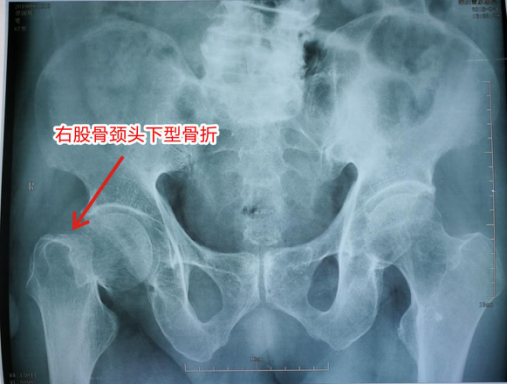

图为老先生术前DR检查结果(右股骨颈头下型骨折)

据了解,这位老人87岁,名叫肖国辉,是坂田上雪村本地村民,由于长期患有高血压病、脊柱侧弯及双踝畸形等疾病,行动不便不幸滑倒,导致右股骨颈头下型骨折,右髋肿胀、疼痛剧烈,卧床不起,于2018年9月4日由家人急送我院外科住院。由于高龄老人受多种疾病的长期困扰,手术难度大,麻醉风险高。但如果不实施手术治疗,高龄老人长时间卧床不起,髋部骨折疼痛难以忍受,还会并发肺部感染和泌尿系感染,以及臀部褥疮,最终很可能死于这些并发症。